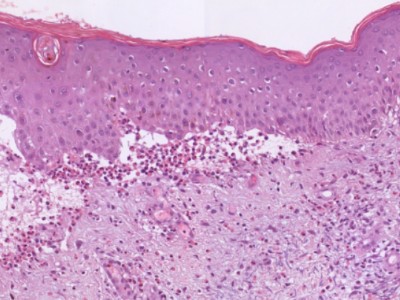

bulleus pemphigoid bulleus pemphigoid (IF) bulleus pemphigoid (PA)

PA-Foto: Sarahkayb - Wikimedia (Creative Commons License 3.0).

De diagnose wordt gesteld op de combinatie van klinisch beeld (stevige blaren), histologisch beeld (subepidermale blaarvorming, dermaal infiltraat, vaak heel veel eosinofielen, soms ook neutrofielen) en immunofluorescenctie onderzoek (IF). De directe immunofluorescentie (DIF) toont lineaire deposities IgG (en C3) langs de basaalmembraan. Indirecte immunofluorescenctie van serum (IIF) is niet noodzakelijk, maar toont bij 70-80% circulerende anti-BM IgG autoantistoffen; er is geen direkt verband met de ziekte activiteit. Indien er gedacht wordt aan epidermolysis bullosa acquisita (EBA) of cicatricieel pemphigoid (CP) dan kan eventueel een salt-split preparaat worden gemaakt. Bij BP zitten de antigenen dan in het dak van de kunstmatige blaar, bij EBA in de bodem (laminine). Zie ook onder diagnostiek bij blaarziekten. Bij bulleuze toxicodermie is de IF negatief.

Histologie lichen planus

ingescande coupe (zoom)

Bron hoge resolutie PA-foto's: Kevin Kwee en Afdeling Pathologie MUMC. Klik op de afbeelding om in te zoomen.